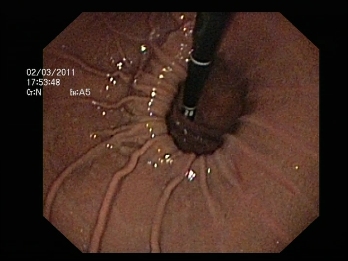

Esofagitis grado II

- Endoscopia digestiva alta (o esofago-gastroscopia): Permite confirmar la presencia de una hernia de hiato y en caso de que exista reflujo gastroesofágico evidenciar la presencia de esofagitis si la hubiera. Permite tomar biopsias para descartar lesiones premalignas en el esófago de Barret.